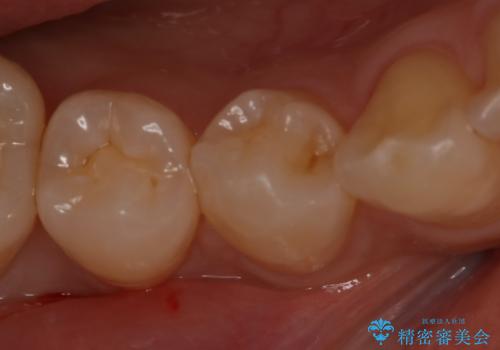

- 右下4番の虫歯治療を希望され来院された患者様です。

セラミックでの治療を希望されたため、切削量・形態を考慮しセラミックインレーでの治療を計画しました。

う蝕を除去した後、CRで裏層した上で形成、印象をしています。

装着時にはラバーダムを使用しています。